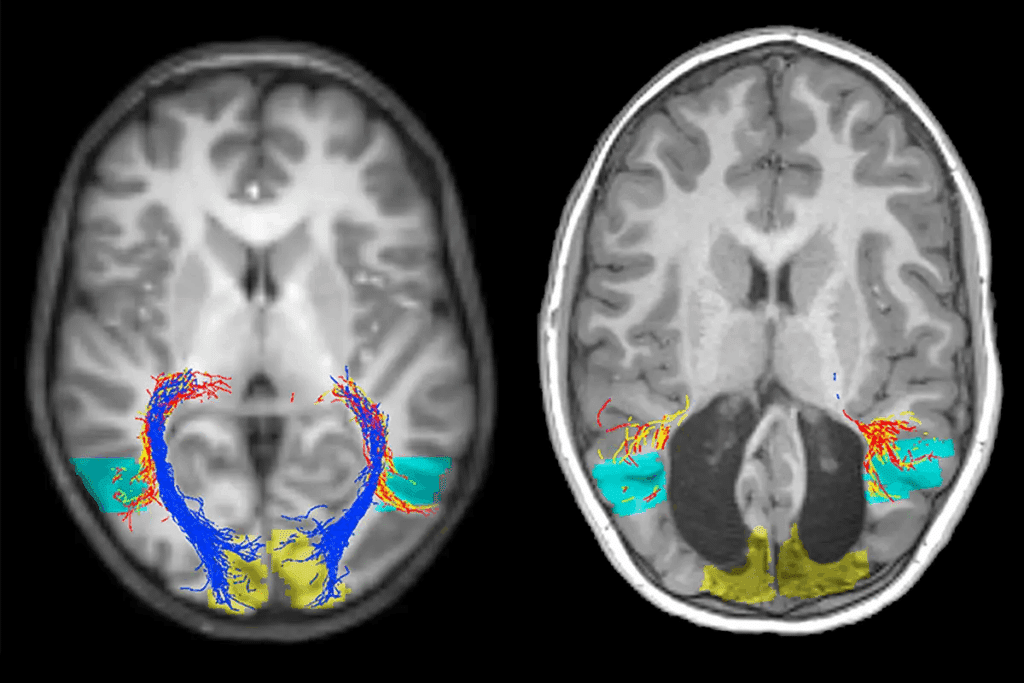

- Functional MRI (fMRI): It spots brain activity by looking at blood flow changes.

- Diffusion Tensor Imaging (DTI): It gives clear images of white matter tracts.

Diffusion Tensor Imaging (DTI)

Diffusion Tensor Imaging (DTI) shows how water moves in tissues. It’s great for seeing brain white matter tracts, which is vital for surgery planning and diagnosing neurological issues.

DTI’s complex processing makes scans longer. Yet, it gives deep insights into brain connections and white matter health. This is super helpful for diagnosing strokes, multiple sclerosis, and brain tumors.